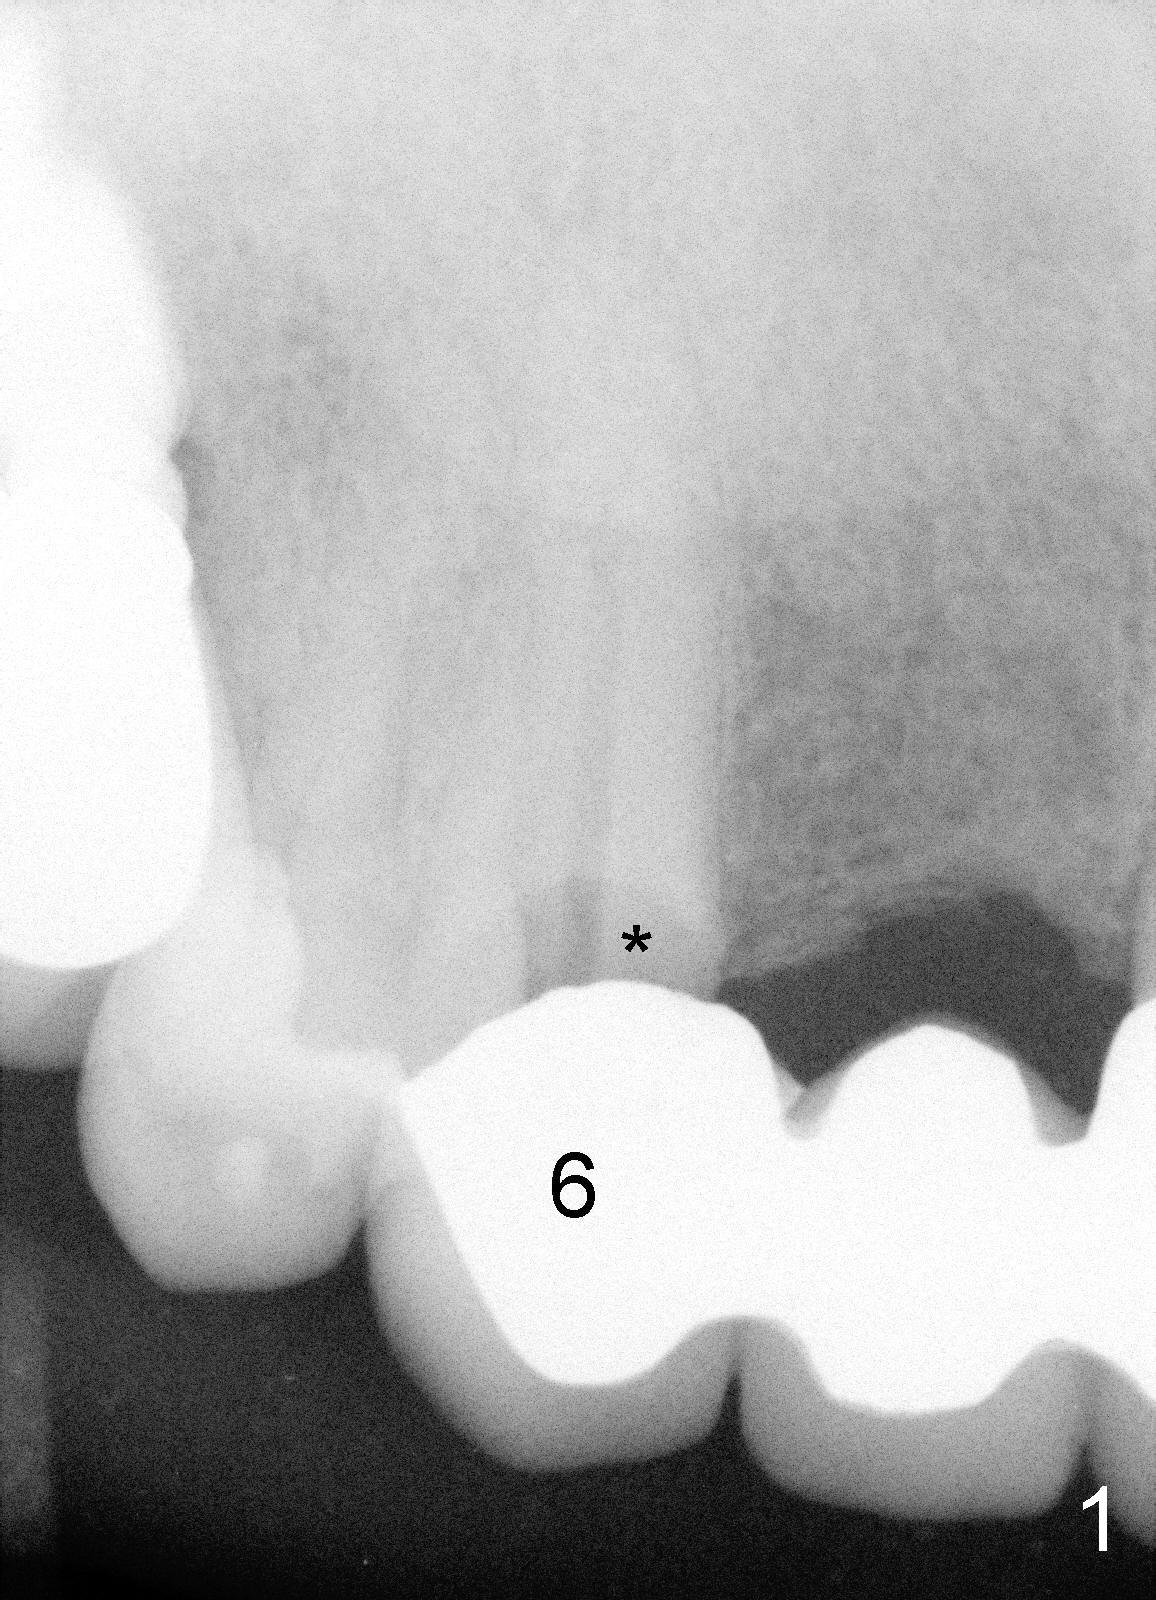

A 73-year-old man feels that upper right bridge is loose. There is subgingival caries (*) under one of its retainers (#6 in Fig.1). CBCT shows that bone volume is sufficient for immediate implant at #6 (Fig.2). When the bridge is sectioned between the pontic #7 and retainer #8, the pontic #7 and retainer #6 complex falls out by themselves. The tooth #6 is deemed nonsalvageable (albeit vital); the labial plate of #7 is atrophic (Fig.3).